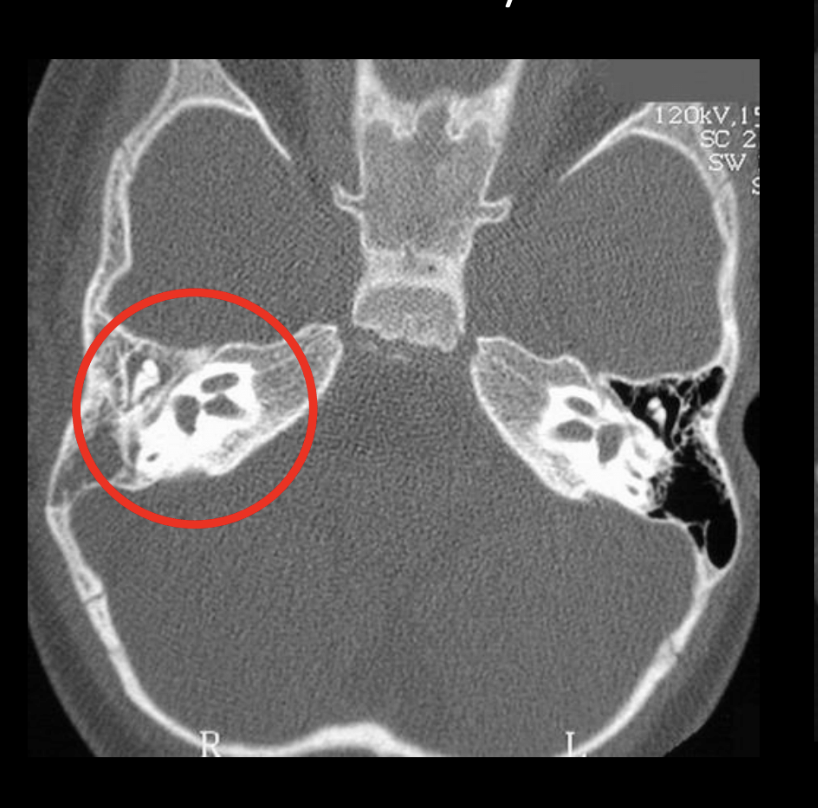

Diagnóstico

24

Q